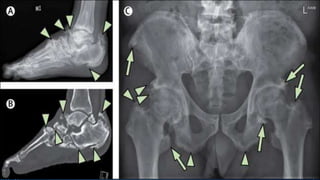

• Imaging Investigation

• A plain lateral X-ray can help to exclude a stress fracture,

and will often show what looks like a bony spur on the

undersurface of the calcaneum.

• 10. • Imaging Investigation • A plain lateral X-ray can help to exclude a stress fracture, and will often show what looks like a bony spur on the undersurface of the calcaneum.